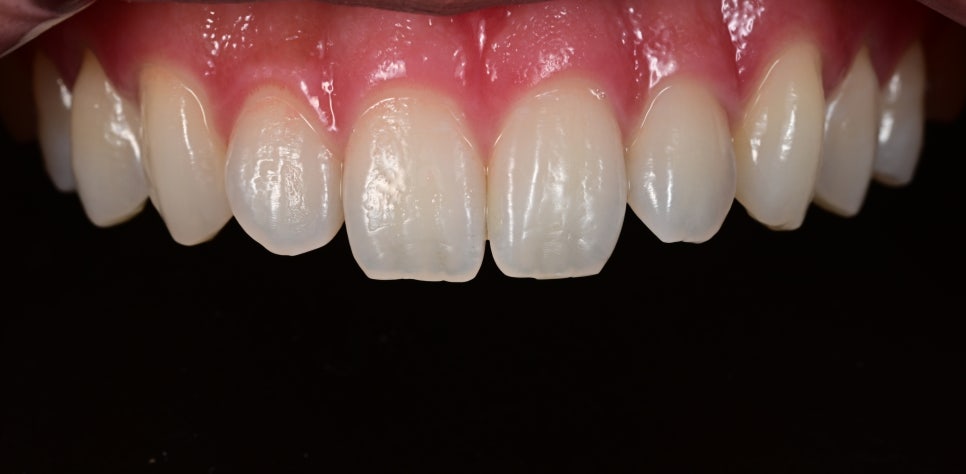

오브제로 시술 후 사진

오브제로 시술 후